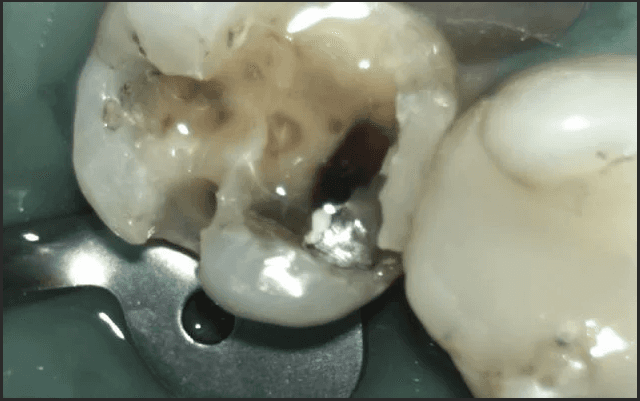

Upon taking the necessary SMART precautions to remove the amalgam as safe as possible, there was considerable amalgam remaining, as well as secondary decay.

After the complete removal of the residual amalgam and decay, composite resin was placed, replicating the natural form of the original tooth.